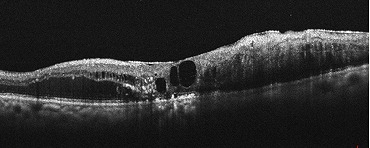

黄斑円孔

中心部分が見えづらくなる(中心暗点)や物がゆがんで見えるなどの症状が生じるとされています。

治療としては、現在のところ、点眼薬や内服薬による治療法はなく、手術(硝子体手術)が唯一の治療法となっています。当院では、必要に応じて連携する医療機関をご紹介しております。